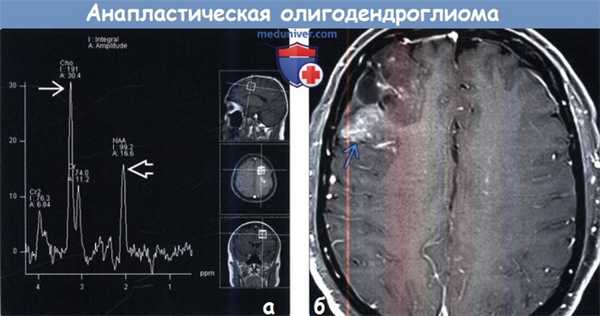

(а) МР-спектроскопия: у того же пациента определяется типичный спектр злокачественной опухоли с заметным повышением пика холина и снижением пика NAA. МР-перфузия и МР-спектроскопия могут быть полезны в предоперационной диагностике, а также оценке состояния пациентов с глиальными новообразованиями после курса лечения.

(б) МРТ, постконтрастное Т1-ВИ, режим подавления сигнала от жира, аксиальный срез: определяется гетерогенный характер накопления контрастного агента объемным образованием правой лобной доли. При хирургической резекции была обнаружена олигодендроглиома grade III. Олигодендроглиомы характеризуются более благоприятным прогнозом, чем «чистые» астроцитомы той же степени злокачественности.

(а) МРТ, постконтрастное Т1-ВИ, аксиальный срез: у пациента, которому проводилось хирургическое лечение, лучевая терапия и терапия темозоломидом по поводу анапластической олигодендроглиомы в левой лобной доле определяются ранее не выявляемые участки накопления контрастного средства. Появление участков контрастирования в ранее неконтрастирующимся объемном образовании очень характерно для прогрессирования заболевания.

(б) МР-перфузия, метод динамической восприимчивости контраста (DSC), цветная карта rCBV, аксиальный срез: определяется повышение относительного объема мозгового кровотока в новых участках контрастирования, что говорит о прогрессировании опухоли.